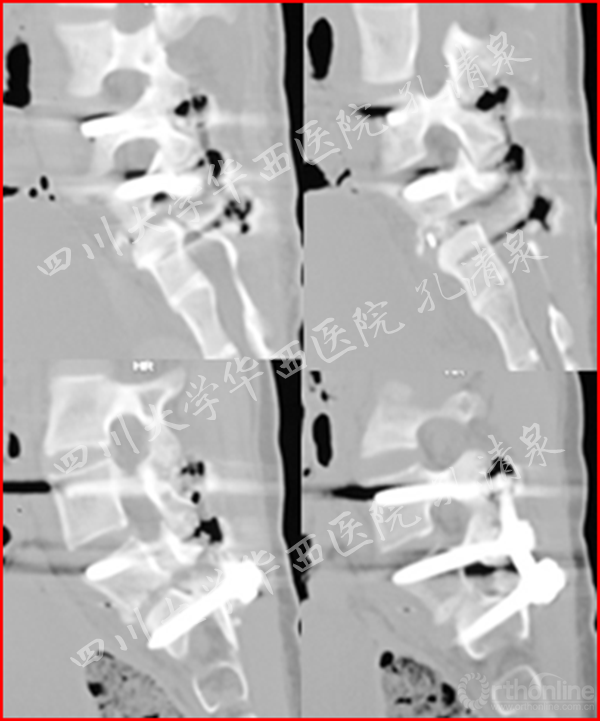

治疗:经后路腰5-骶1固定、腰5滑脱、骶1骨骺复位、椎管减压、后外侧植骨融合术,术后患者双下肢麻木消失,肌力恢复正常,术后2月复查发现轻度的腰椎侧凸,术后三年复查存在27°的腰椎侧凸,取出内固定,术后六年半时CT复查示腰5和骶1高度增加2mm,残留27°的腰椎侧凸。

图9 术后一周复查见滑脱复位良好,无侧凸;术后两月复查,复位情况良好,可见轻微腰椎侧凸